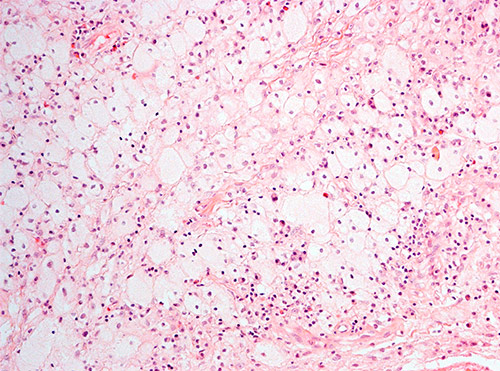

Histologisk undersøkelse hadde vist inflammatorisk prosess med mange makrofager, spredtliggende og enkelte grupper av lymfoide celler, spredte plasmaceller, nøytrofile og eosinofile granulocytter (fig 1). Atypiske celler, granulomatøs betennelse eller vaskulitt var ikke påvist. Spesialfarging for sopp, bakterier og mykobakterier var negativ. Ved rutinemessig immunhistokjemisk undersøkelse var makrofagene positive for CD68. De små lymfoide cellene var B-celler positive for CD20 samt T-celler positive for CD4 og CD8.

Ved ny gransking ble det poengtert at makrofagene hadde rikelig med lyst skummende cytoplasma, forenlig med skummakrofager. Immunfenotyping viste at de CD68-positive makrofagene var negative for CD1a og S100. Patolog konkluderte med at det morfologiske bildet passet med Erdheim-Chesters sykdom.